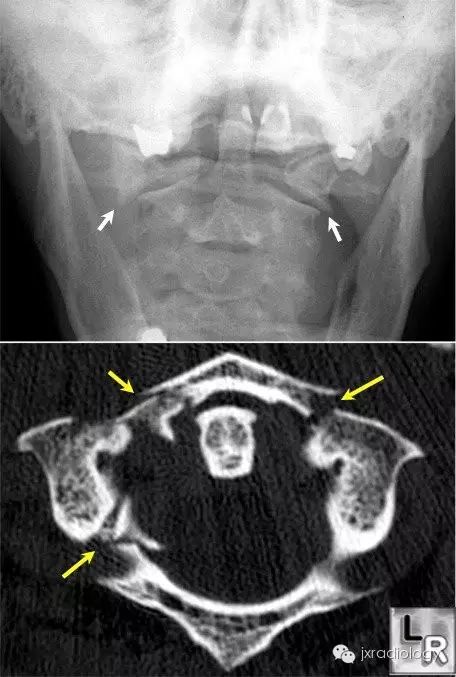

寰椎骨折又名Jefferson骨折(因由Jefferson于1920年首次报道,故此命名)。环形的寰椎遭受轴向压缩和头部向后、下转伸时,暴力经枕骨髁作用于寰椎侧块,并引起寰椎骨环爆裂(散)骨折。寰椎的前弓与后弓双侧骨折,以致侧块被挤压而向四周分离

主要介绍颈椎开口位的X线平片表现:开口位可发现寰椎左右增宽,且与齿突的距离双侧常呈不对称状。如双侧侧方移位总和超过7mm者,则表示寰椎横韧带断裂、寰椎骨折。

正位与齿状突对比似双侧开门样增宽,为此加深记忆,故得此名,如有不妥,敬请谅解(小编)。